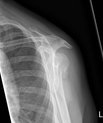

An arm in a sling cures a shoulder fracture just as well as an operation with plates and screws. This is shown by a comprehensive study from Aarhus…